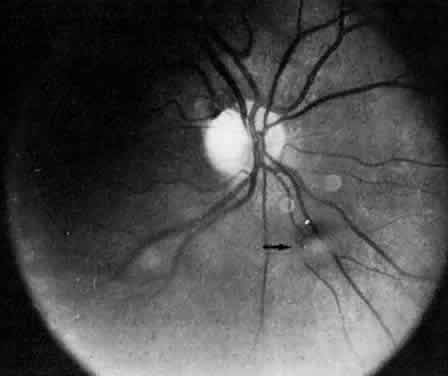

Retinal detachment, vitreous hemorrhage, optic disc swelling, and dragging of the optic disc vessels caused by contraction and neovascularization of cyclitic membranes occur in less than 10% of cases.13,52,53 Periphlebitis has been reported in about 21% of cases.52 Neovascularization of the optic disc53–55 and peripheral retina56 can also occur (Fig. 7). Coat's-like response has been reported in pars plantitis.57 Band keratopathy, glaucoma, and retinoschisis may develop as late sequelae in pars planitis.13

Fig. 7. Pars planitis. Fluorescein angiogram of neovascularization of the optic disc.

Fig. 8. Posterior pole in a patient with intermediate uveitis. The arrow indicates a vitreous opacity resembling a puffball.